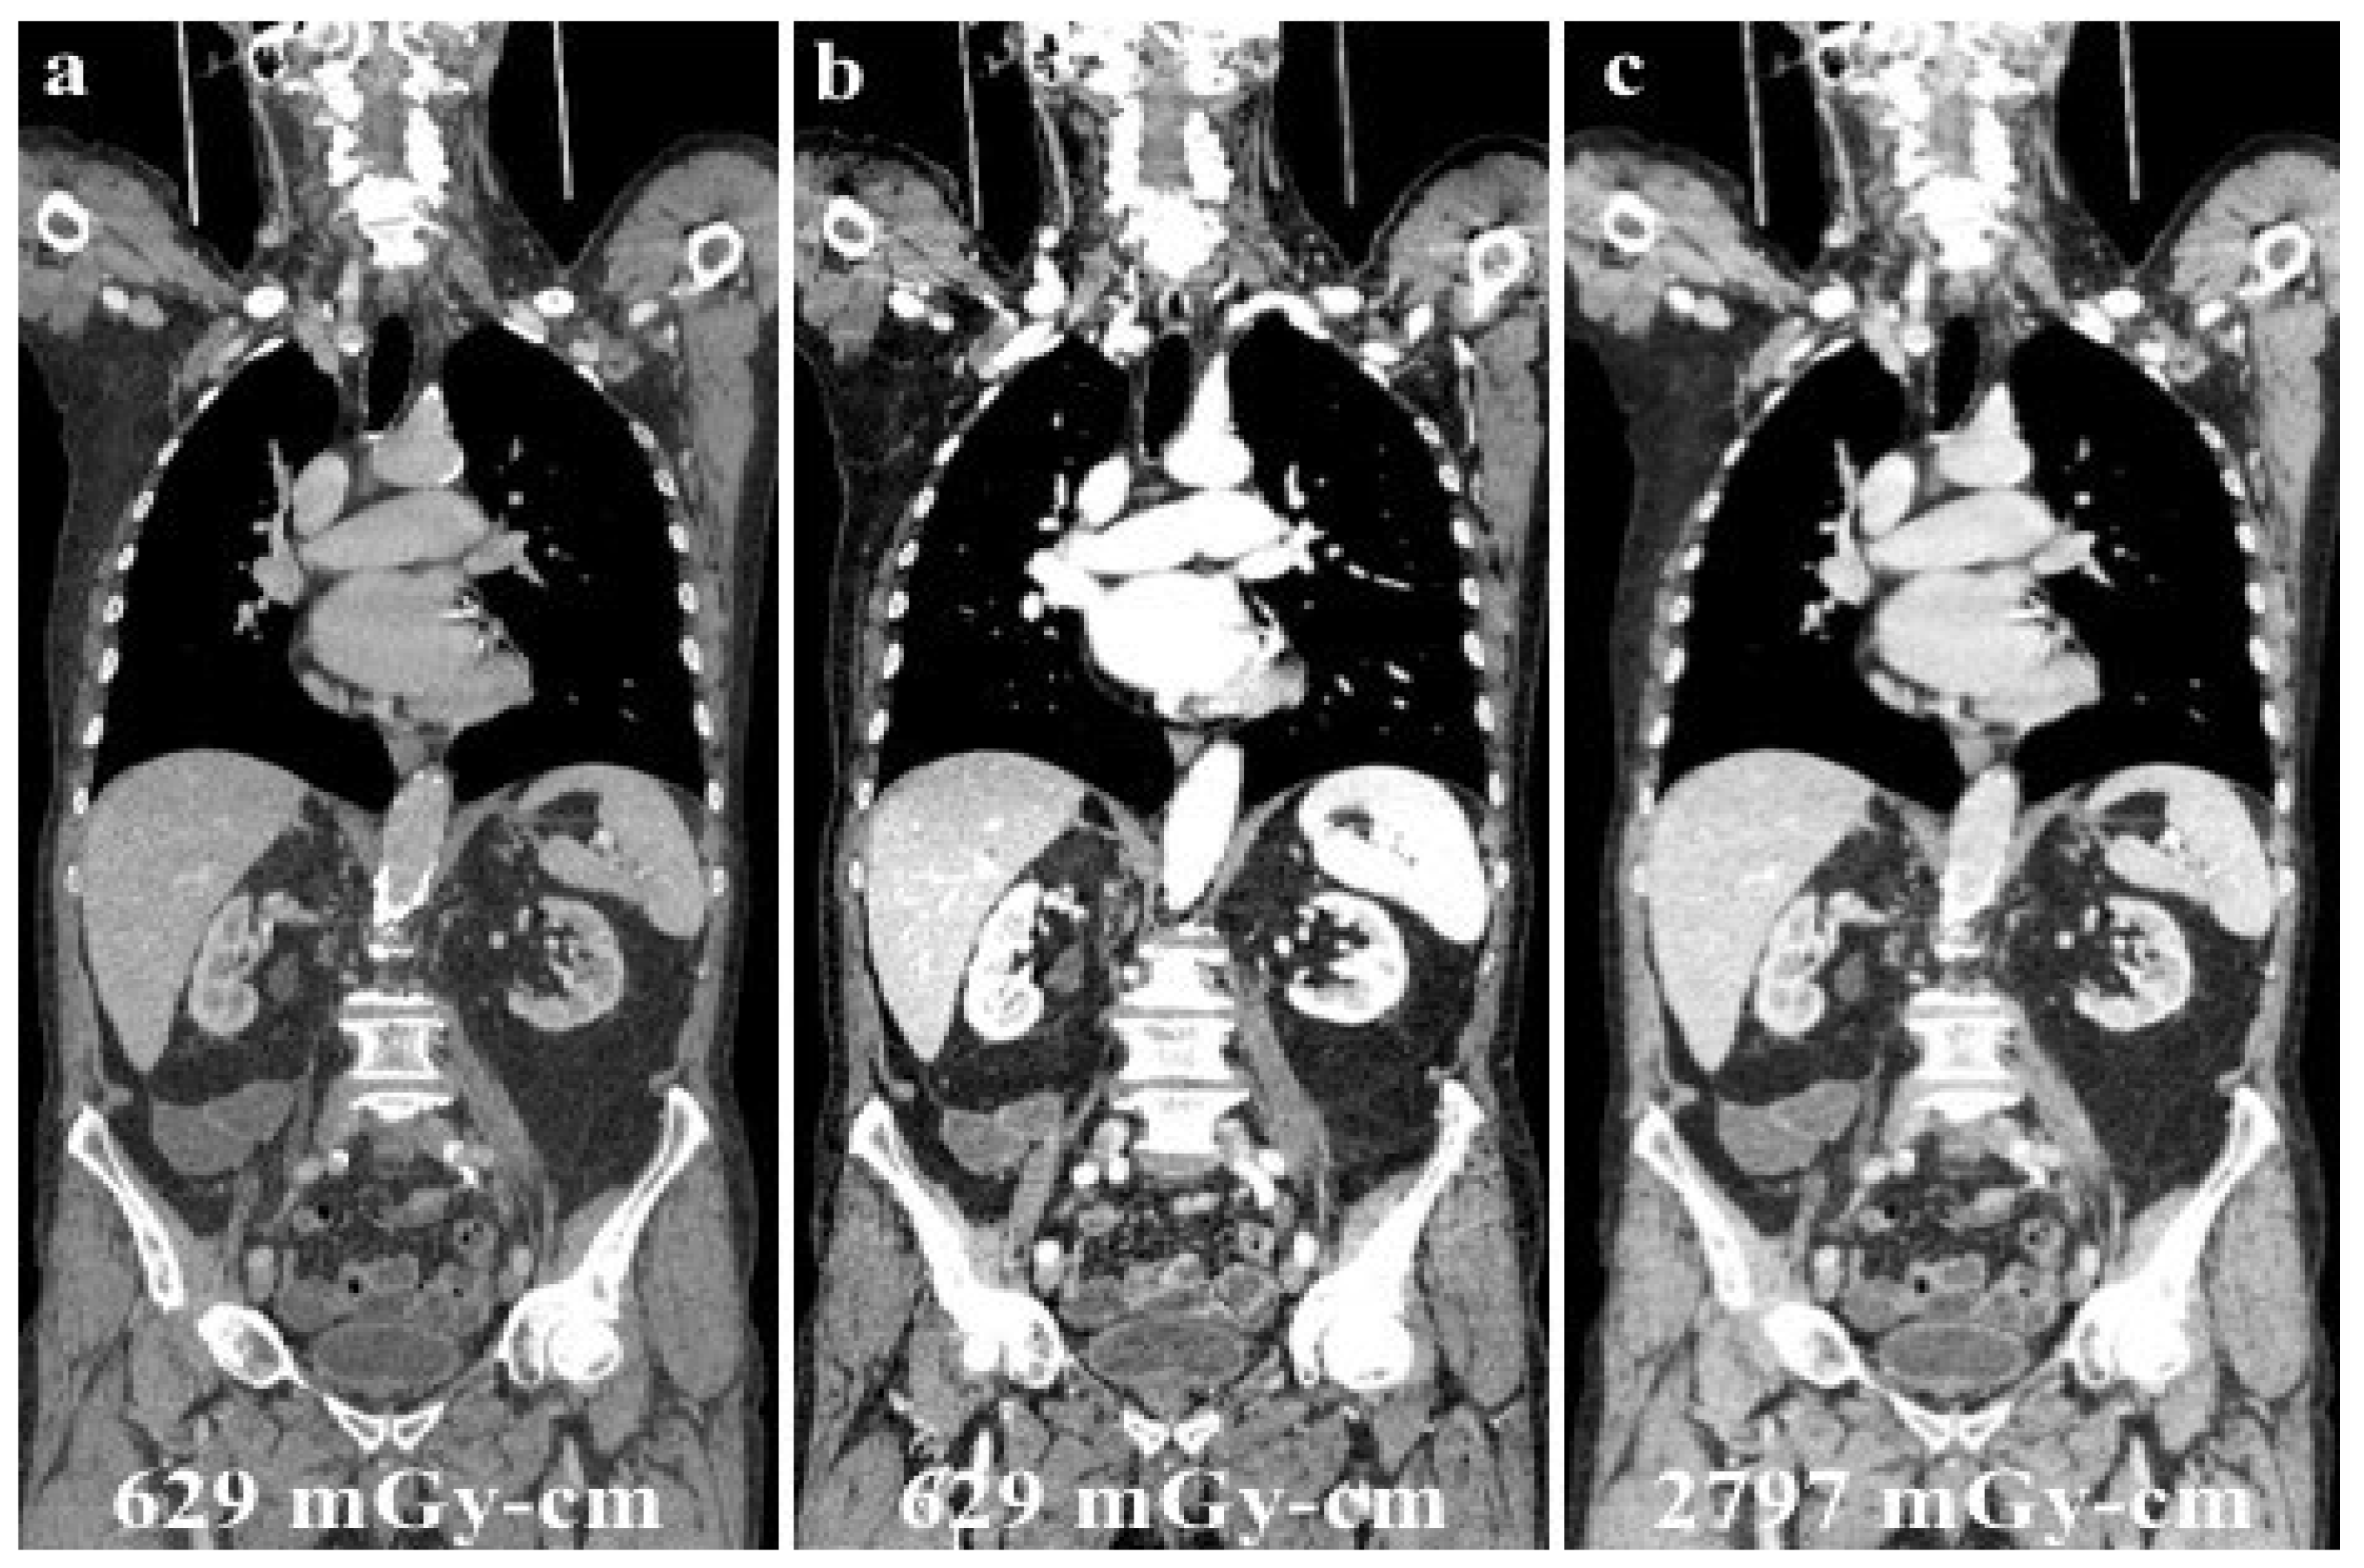

Since its use in clinical practice, the issue of patient dose exposure with DECT has been the focus of several studies in the literature. Dual-energy CT has been mistakenly associated with exposure to a “double” dose of ionizing radiation, only because of the word “double” in its name. However, many series reported the feasibility of DECT without increasing the radiation dose exposure of the patient, as illustrated in the case shown in Figure 6 [60,61].

Figure 6.

A young male patient receiving chemotherapy for a primary mediastinal large B-cell lymphoma submitted to routine DECT follow-up after 70 mL of contrast media administration (a), and evaluated at low energy levels (40 keV, (b)) to reduce the iodine load and maintain a high diagnostic accuracy. Low energy levels (b) were as accurate as SECT (c) in confirming no recurrence of disease with considerable advantages in the patient’s dose exposure (total DLP: (a,b), 629.18 mGy-cm; (c), 2797.25 mGy-cm).